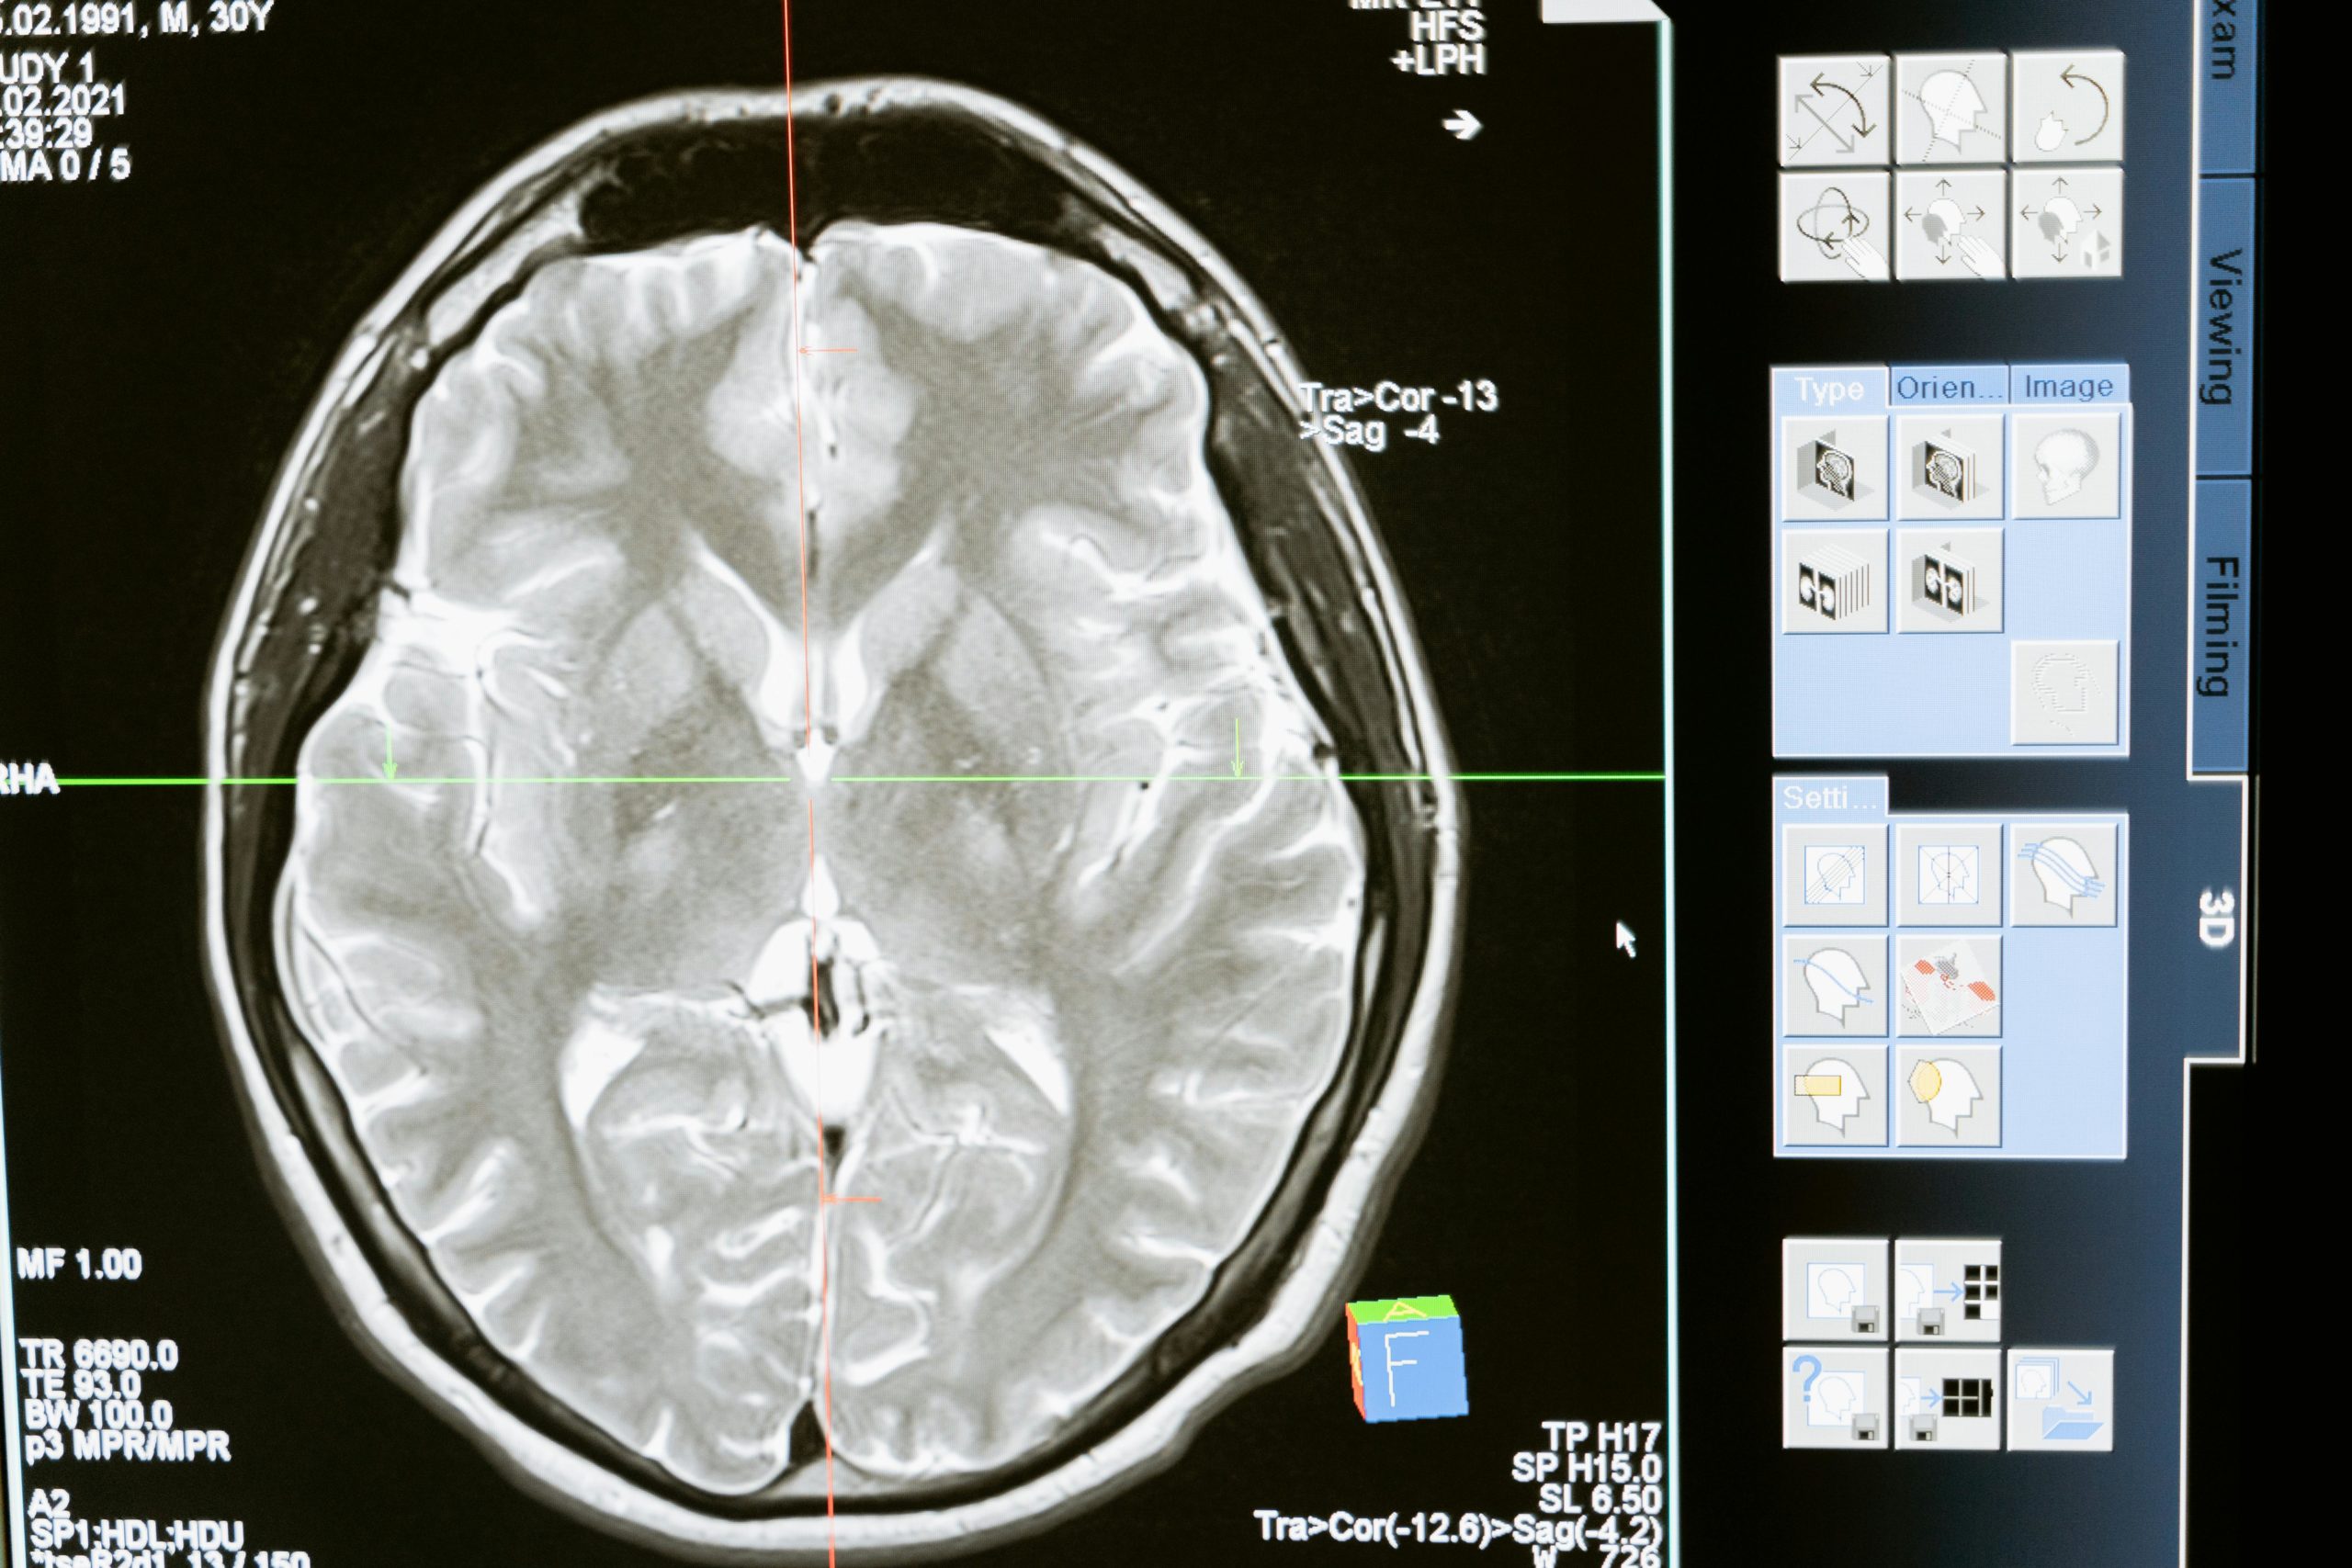

Gehirnforscher nutzen verschiedene Methoden, um im lebenden Menschen Einsicht in die Hirnaktivität zu gewinnen. Die wichtigsten Verfahren sind bildgebende Neuroimaging-Methoden und das EEG.

• MRT (Magnetresonanztomografie): Mit dem MRT können Forscher die Struktur und teilweise auch die Aktivität des Gehirns messen. Normale MRT-Bilder zeigen z. B. das Volumen von Hirnarealen oder bestimmen, ob die Anatomie normal ist. In der Lernforschung verwendet man vor allem das fMRT (funktionelle MRT). Dabei bleibt die Person in einer Röhre liegen und löst Aufgaben, während das Gerät Blutfluss und Sauerstoffverbrauch misst. Aktive Hirnregionen „leuchten“ dadurch in den Bildern auf.